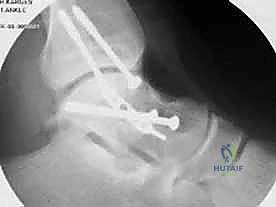

المرحلة الرابعة: التثبيت الداخلي (Internal Fixation)

بمجرد التأكد من أن العظم عاد لشكله الطبيعي تماماً، يتم استبدال الأسلاك المؤقتة بتثبيت دائم. يستخدم الدكتور هطيف أحدث الغرسات الطبية العالمية:

* مسامير التيتانيوم المجوفة (Cannulated Screws): مسامير قوية جداً يتم إدخالها عبر العظم لضغط أجزاء الكسر معاً.

* المسامير بدون رأس (Headless Compression Screws): تُستخدم في المناطق المغطاة بالغضروف، حيث تُدفن بالكامل داخل العظم لكي لا تحتك بالمفصل وتسبب تآكلاً.

* الشرائح المعدنية الدقيقة (Mini-Plates): تُستخدم أحياناً لتدعيم التثبيت في حالات التفتت الشديد (Comminution) حيث لا تكفي المسامير وحدها.

يتم وضع المسامير عادة من اتجاهين (من الأمام للخلف، ومن الخلف للأمام) لإنشاء هيكل ميكانيكي صلب يتحمل الضغوط.

المرحلة الخامسة: التحقق الإشعاعي الفوري والإغلاق

قبل إنهاء العملية، يستخدم الدكتور هطيف جهاز الأشعة السينية المتحرك داخل غرفة العمليات (C-arm Fluoroscopy) لأخذ صور متعددة والتأكد من:

1. المحاذاة المثالية للكسر.

2. عدم وجود أي فجوات أو درجات في السطح المفصلي.

3. الطول والموقع الصحيح للمسامير (للتأكد من أنها لا تخترق المفاصل المجاورة).